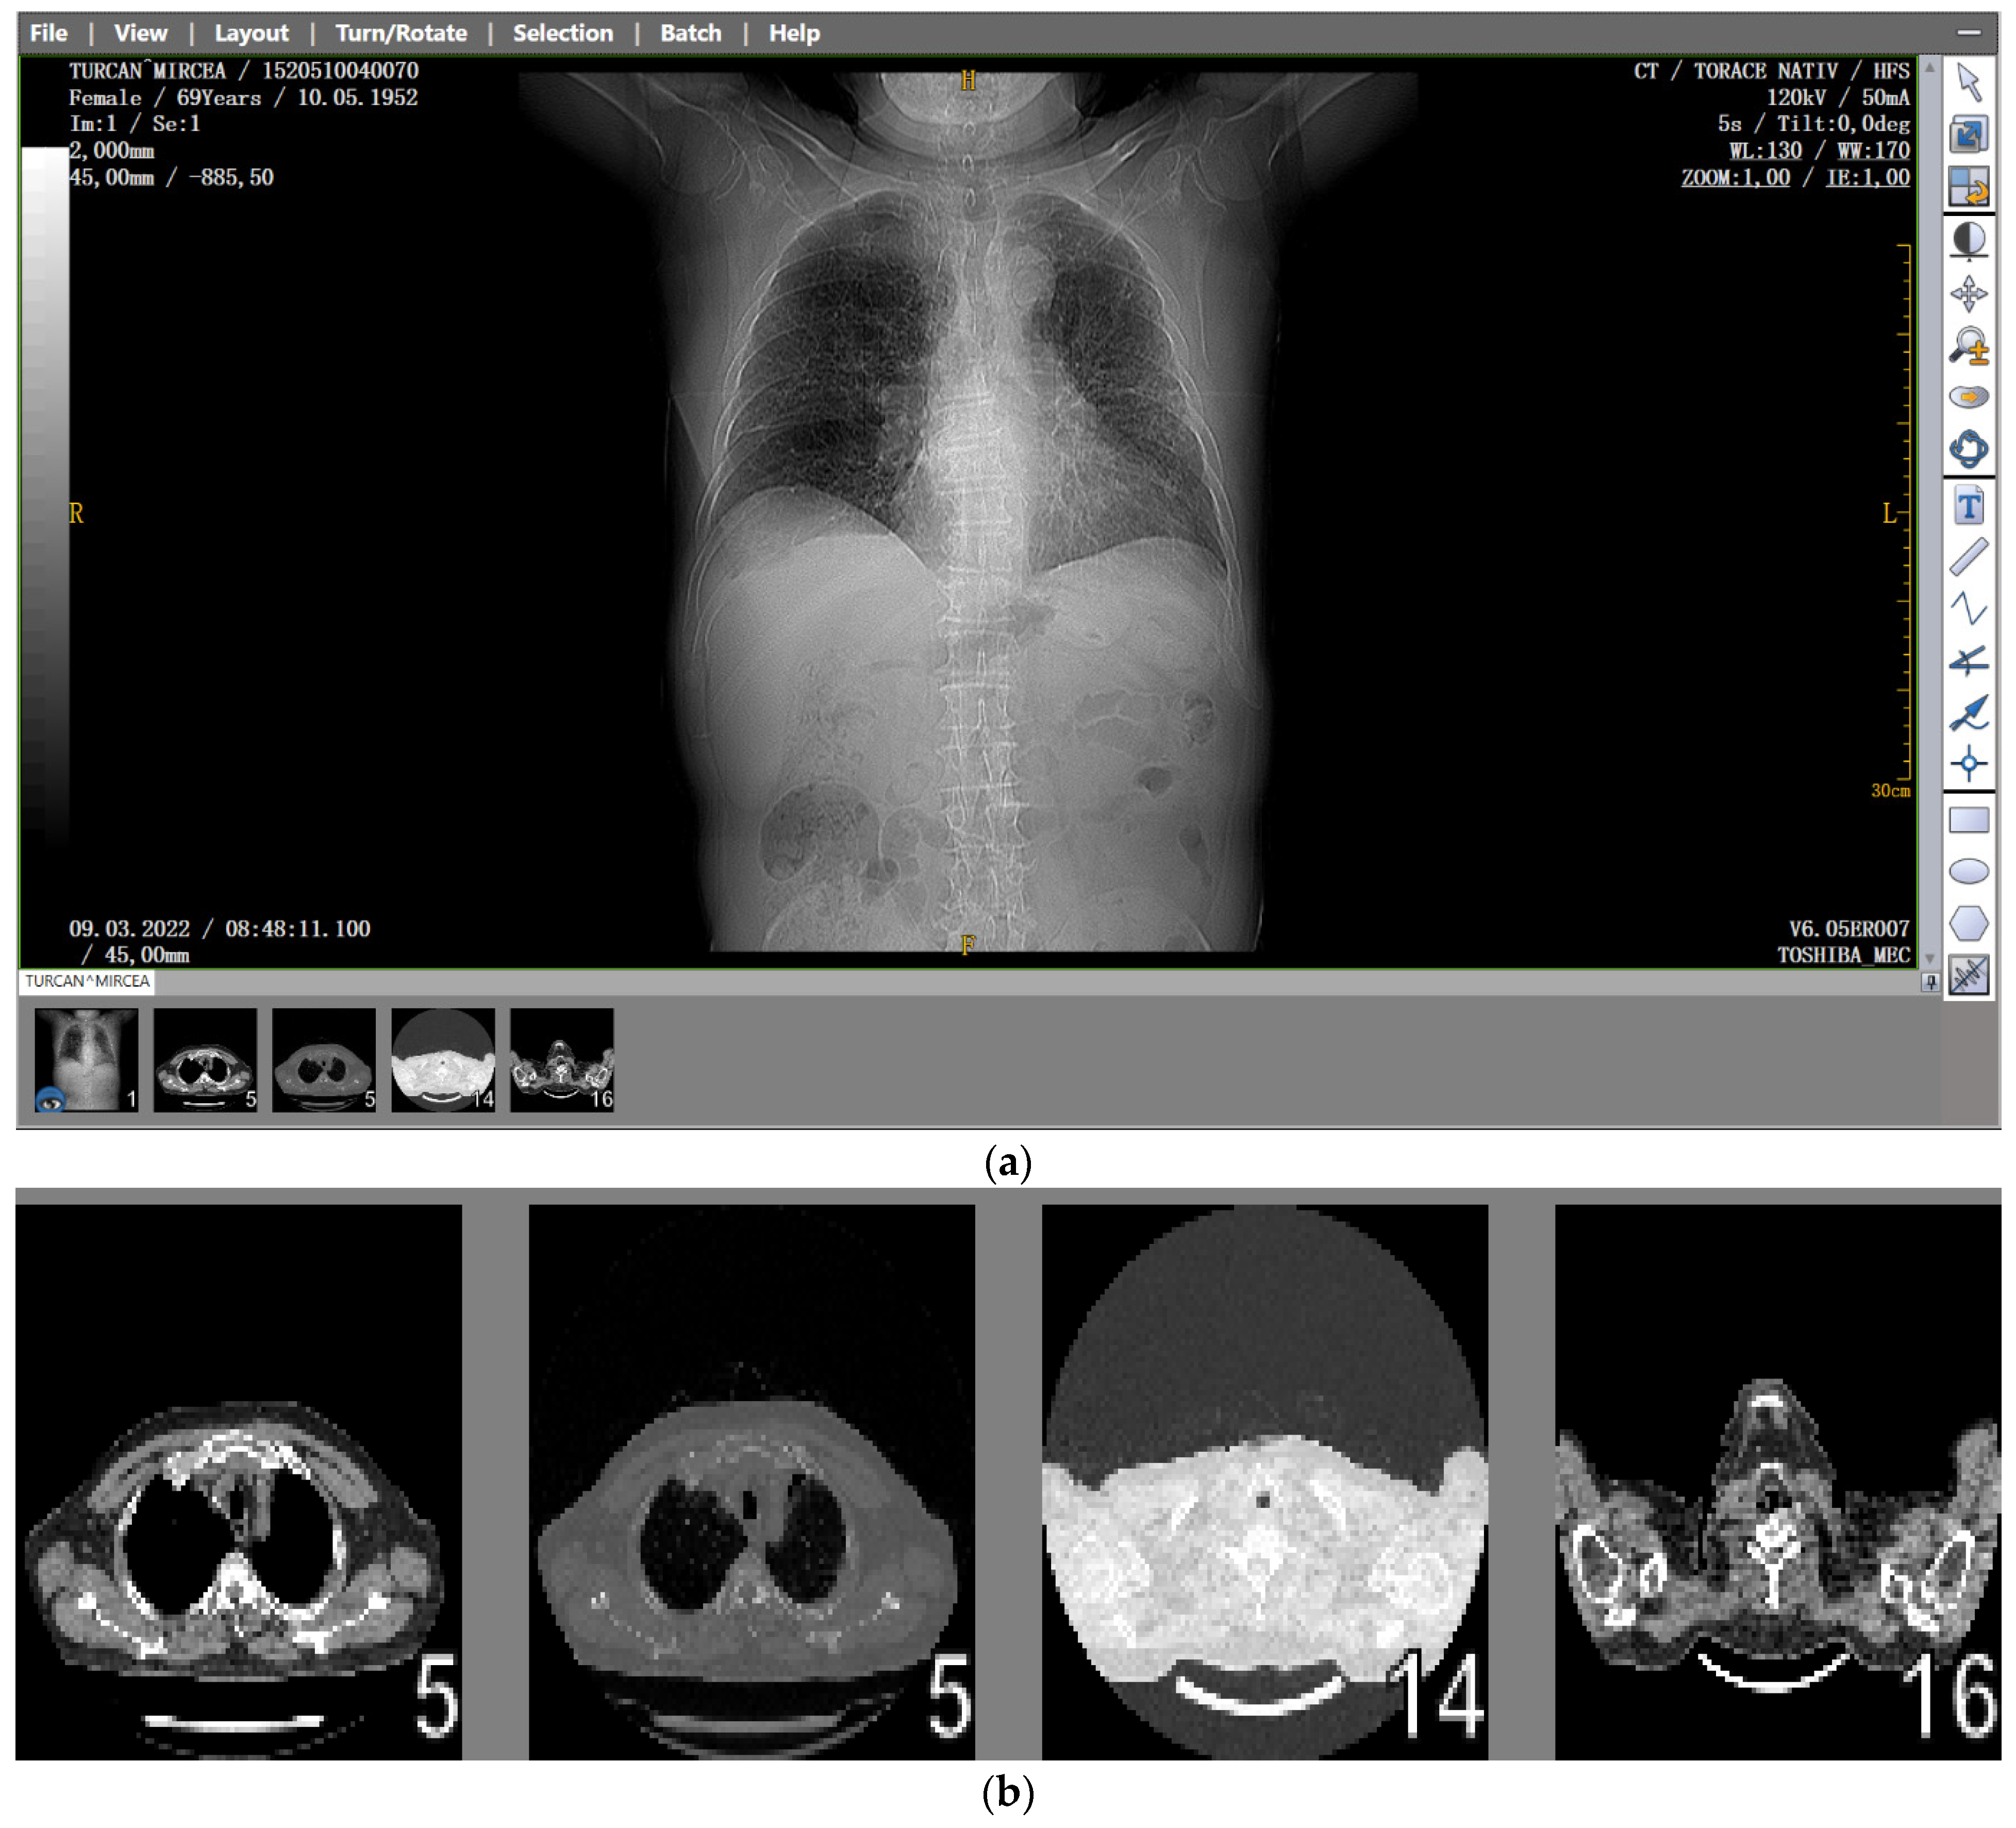

Several patients with a preliminary diagnosis of COVID-19 were tested using CT imaging with the contrast substance OMNIPAQUE 350. The pulmonary CT images obtained for each patient, along with their detailed fractal analysis, are presented in Figure 1, below.

3.1. Patient Code: MT

Date of performing the pulmonary investigation: 9 March 2022.

Figure 1. (a) The CT scan image of a 69-year-old patient who underwent a chest CT examination due to suspicion of COVID-19 in the lungs. (b) A schematic representation of the pre-processing phases of the patient’s CT image (2D), which was resampled to an isomorphic resolution. The indices 5, 14, and 16 represent the numbers of the slices in order.